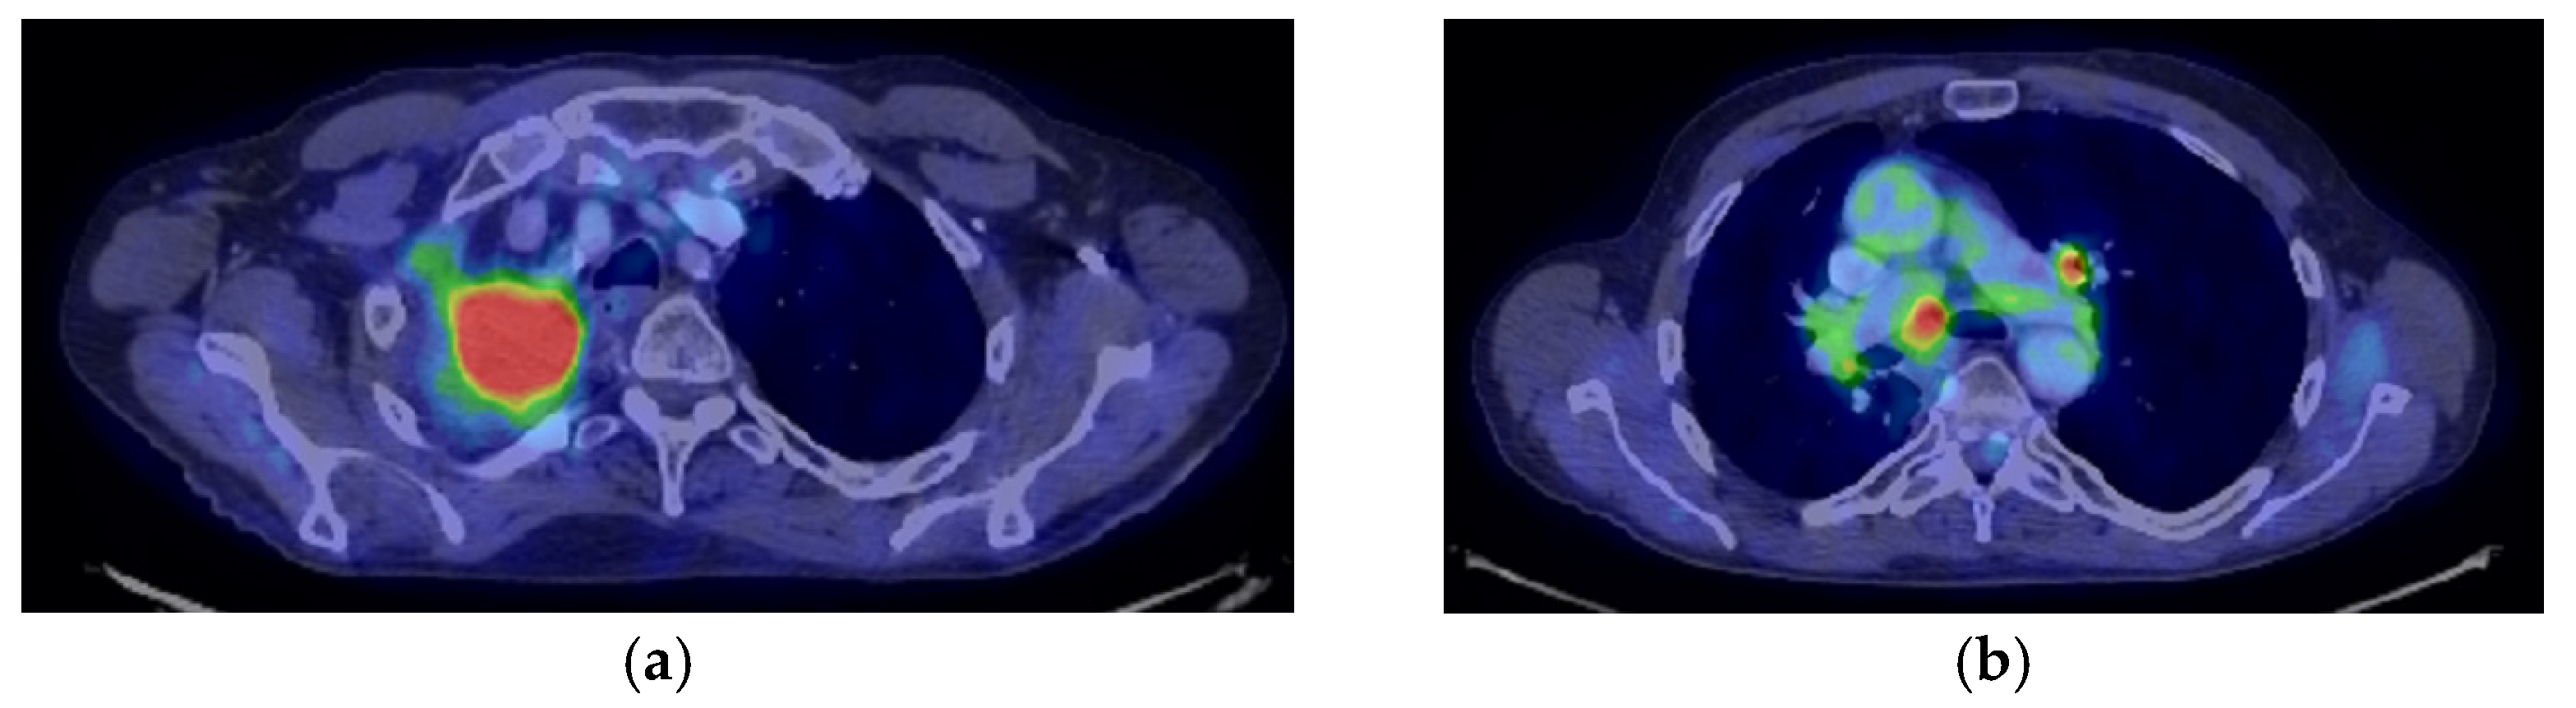

2. Case Presentation

2.1. Systemic Third-Line Therapy (4xDocetaxel) Was Initiated 04–07/2020

2.2. Monitoring 2022: Oncological Commission 1910/16.08.2022

2.3. Oncological Committee 07/25/2023 Recommended

- Consider rescue re-irradiation (SBRT), taking into account the current primary tumor dimensions of 24 × 34.2 mm on PET CT from 06/2023 and also the total dose previously administered (08–09/2020), the previously applied fractionation, the time between the two irradiations, the cellular repair time and the dose constraints for the organs at risk.